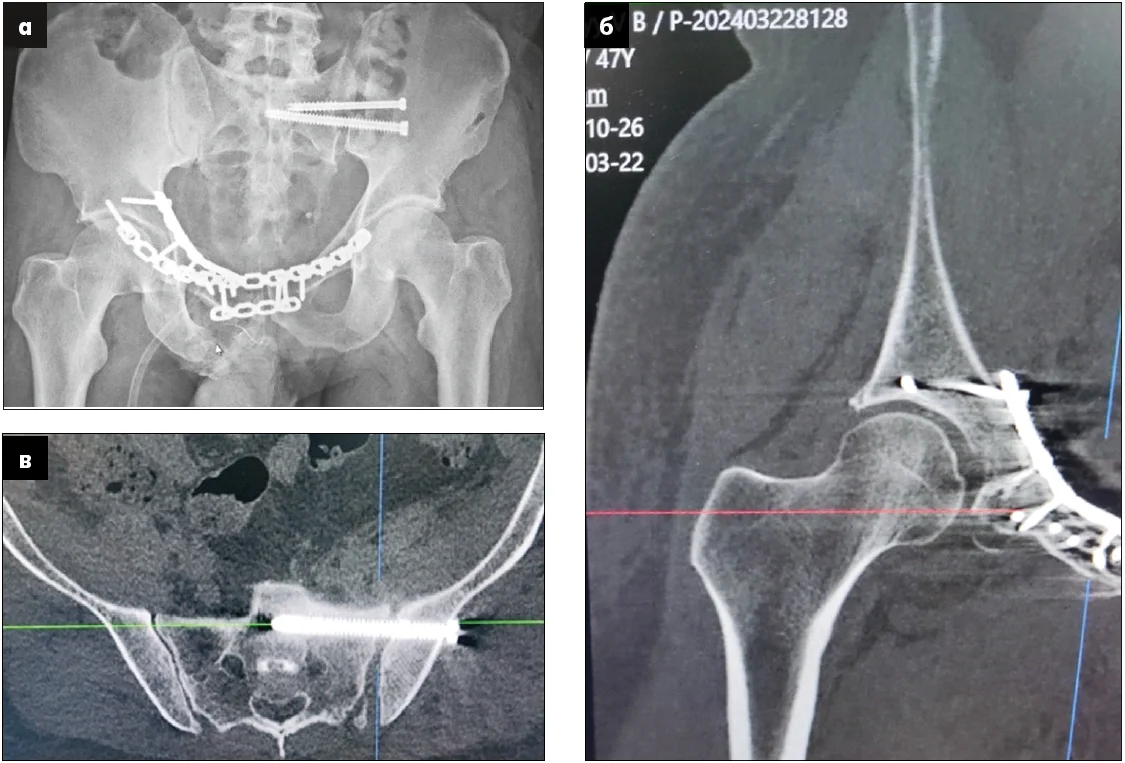

Рис. 5. Зображення після втручання: а – рентгенограма в передньо-задній проєкції;

б – КТ-зображення, що ілюструє проведення фіксуючих гвинтів поза межами порожнини кульшового суглоба; в – КТ-сканування правильного положення гвинта, який фіксує крижово-клубове з’єднання в напрямку «клубова кістка – тіло S1»